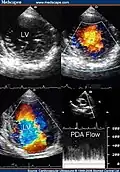

Two-dimensional apical four chamber and parasternal short axis images at the level of the ventricles show dilatation of both ventricles, multiple trabeculae and intertrabecular recesses in inferior, lateral, anterior walls, middle and apical portions of the septum and apex of the left ventricle. [1] -

Transthoracic two-dimensional study with color and continuous wave Doppler shows left ventricular noncompaction associated with patent ductus arteriosus (PDA). [2] -

Two-dimensional parasternal and color Doppler images at the level of both ventricles that show the noncompacted:compacted wall ratio and how the color enters the intertrabecular recesses [4]